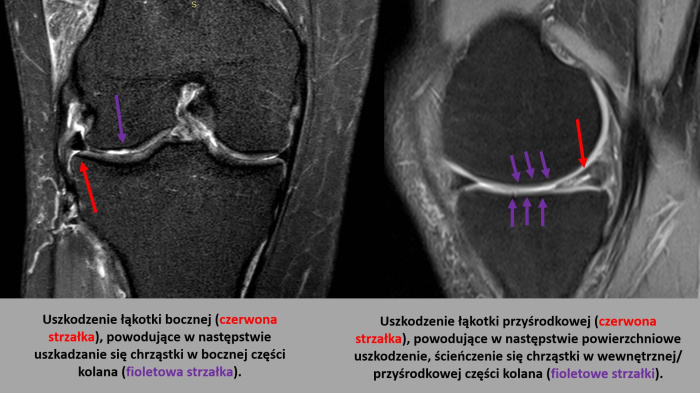

Nienaprawione uszkodzenie łąkotki może prowadzić do postępującego uszkadzania się chrząstki stawowej, a w konsekwencji do rozwoju choroby zwyrodnieniowej stawu kolanowego. Dlatego w przypadku urazu łąkotki warto jak najszybciej skonsultować się ze specjalistą ortopedą, który dobierze odpowiednią metodę leczenia.